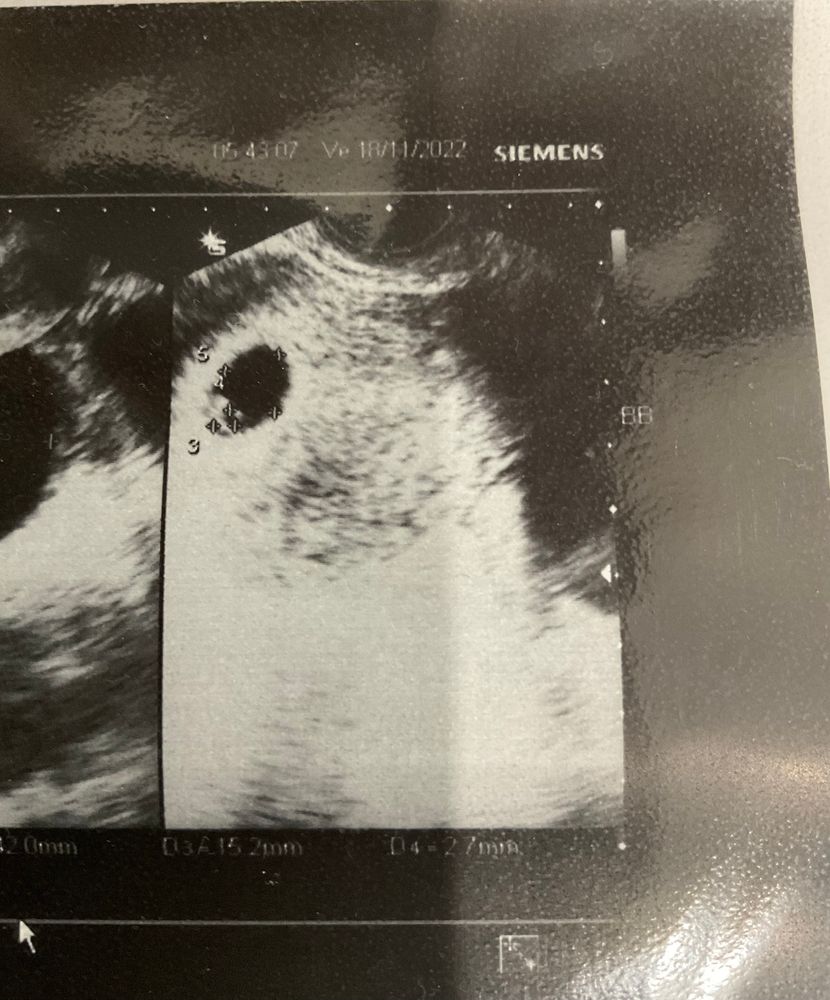

Чудо и шок 🙀 Оставляю на память фото узи

Юлия Гончаренко, да уж, я могла предположить и была готова к самому худшему, но двойни я вообще не ожидала, прямо как увидела, сказала «охринеть», врач говорит «согласна, если бы прошлое узи не я делала, то решила бы, что там была ошибка». Дальше меня просто трясло 😅

Христа, здравствуйте) да, до 7 недели видели только 1 ПЯ, они прямо друг за другом оказались и с разницей в 3 дня (с ней же так и растем), видимо поэтому и не заметили